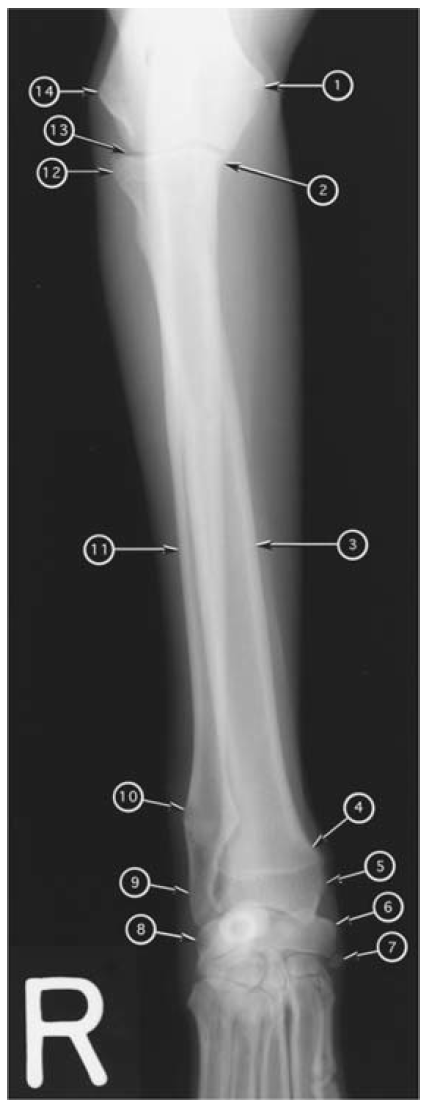

4

Q

Caudocranial radiograph of canine humerus

What number?

- Clavicle

- Trochlea of humeral condyle

- Capitulum of humeral condyle

- Medial epicondyle of humerus

- Lateral epicondyle of humerus

- Greater tubercle of humerus

- Lesser tubercle of humerus

- Deltoid tuberosity

- Supratrochlear foramen of humerus

- Medial coronoid process of ulna

- Acromion of scapula

A

1. Acromion of scapula

2. Greater tubercle of humerus

3. Deltoid tuberosity

4. Supratrochlear foramen of humerus

5. Lateral epicondyle of humerus

6. Capitulum of humeral condyle

7. Medial coronoid process of ulna

8. Trochlea of humeral condyle

9. Medial epicondyle of humerus

10. Clavicle

11. Lesser tubercle of humerus